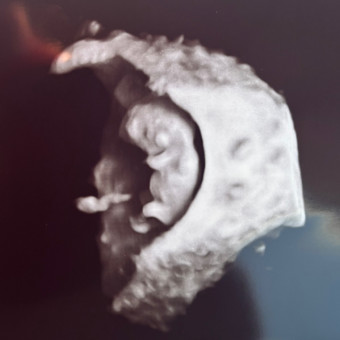

Baby Bogart#2!!

Elena & Drake Bogart

Summerset, SD

September 2, 2026